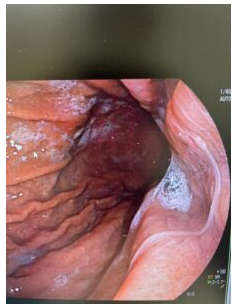

胃カメラ検査を開始すると、食道から胃に入ってすぐにアニサキス虫体を発見!

鉗子(組織をつまむ器材)でアニサキスをつまみます。